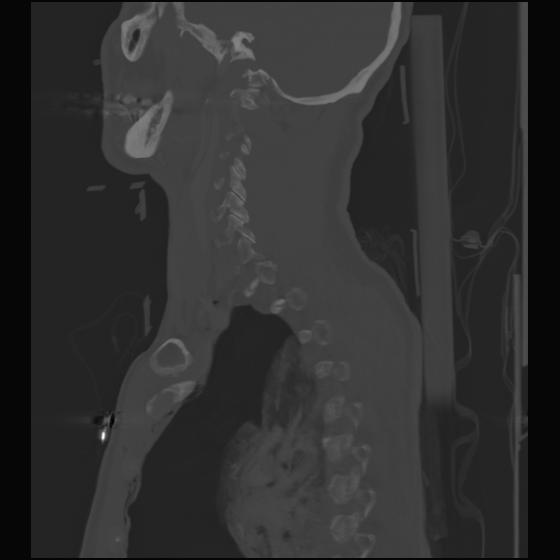

24 ANGIO,CE,Sag-MIP,5.000,ANGIO,Sag-MIP,